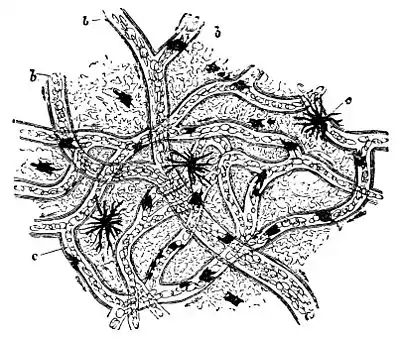

Physical capillary force is not generally regarded as an active force in the circulation. But there is an admitted force in the capillaries, resulting from the attraction of the tissues for the arterial blood, containing the required oxygen and nutriment. "The vital condition of the tissue becomes a factor in the maintenance of the circulation." It is this force, primarily, which adapts the amount of blood to the varying needs of any organ; the nervous system regulates the supply by varying the caliber of the vessels.

Under the influence of nerve-force, the walls of the arteries and capillaries are usually somewhat contracted. The withdrawal of nerve stimulus allows the tubes to relax, which consequently permits more blood to pass through, or to accumulate, and perhaps add color to